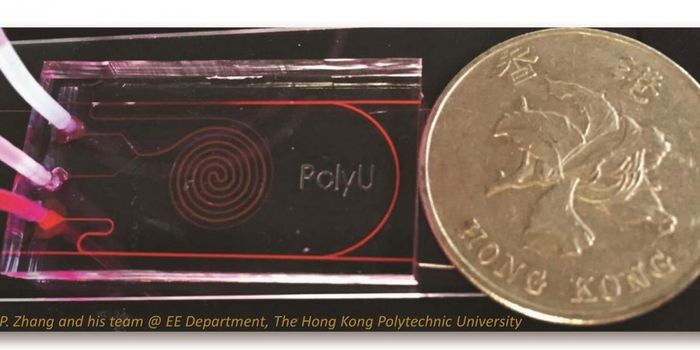

NOV 02, 2016Chemistry & PhysicsDiagnosing Sepsis Earlier to Save Lives Using Microfluidics